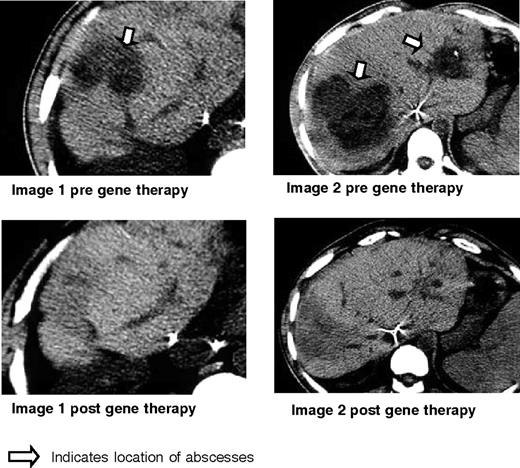

As shown in Figure 7, patient 1 demonstrated resolution of his liver abscesses after gene therapy. Near the end of his prolonged course of antibiotic therapy for liver abscess (8 months after gene therapy), the patient developed an infection of the central venous catheter that resolved quickly after removal of the catheter plus a short course of antibiotics. For the next 2 years (now 34 months after gene therapy), this patient has been free of any infection and remains well on standard CGD antimicrobial prophylaxis.

Clinical results for patient 1. Shown here are the CT scans obtained before gene therapy and 6 months after gene therapy for patient 1 who had biopsy-proven Staphylococcal aureus liver abscesses as indicated by the arrow. These disappeared, leaving only some scarring and regenerating liver as shown in the corresponding post films.